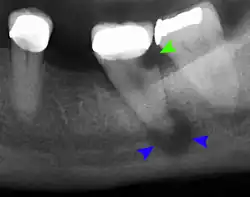

Periodontal abscess

Lateral periodontal abscess (blue arrows) due to a fracture (green arrows)

A periodontal abscess (lateral abscess) is a collection of pus that forms in the gingival crevices, usually as a result of chronic periodontitis where the pockets are pathologically deepened greater than 3mm. A healthy gingival pocket will contain bacteria and some calculus kept in check by the immune system. As the pocket deepens, the balance is disrupted, and an acute inflammatory response results, forming pus. The debris and swelling then disrupt the normal flow of fluids into and out of the pocket, rapidly accelerating the inflammatory cycle. Larger pockets also have a greater likelihood of collecting food debris, creating additional sources of infection.[21]: 443

Periodontal abscesses are less common than apical abscesses, but are still frequent. The key difference between the two is that the pulp of the tooth tends to be alive, and will respond normally to pulp tests. However, an untreated periodontal abscess may still cause the pulp to die if it reaches the tooth apex in a periodontic-endodontic lesion. A periodontal abscess can occur as the result of tooth fracture, food packing into a periodontal pocket (with poorly shaped fillings), calculus build-up, and lowered immune responses (such as in diabetes). Periodontal abscess can also occur after periodontal scaling, which causes the gums to tighten around the teeth and trap debris in the pocket.[21]: 444–445  Toothache caused by a periodontal abscess is generally deep and throbbing. The oral mucosa covering an early periodontal abscess appears erythematous (red), swollen, shiny, and painful to touch.[22]